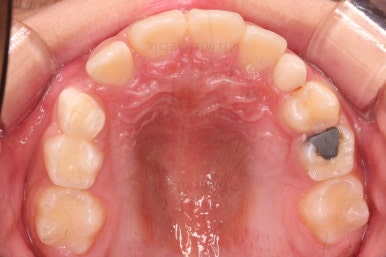

무려 4개월 만에 부산어린이교정 치료가 종료되었습니다.

앞니의 교합이 매우 안정적이여서 치료를 끝냈고요.

전후 비교해 보겠습니다.

반대교합이 완벽히 개선되면서 주걱턱으로 보였던 얼굴형태도 완벽히 개선되었고요.

한 쪽으로 치우치던 아래턱의 위치도 돌아오면서 비대칭이 개선되었습니다.

심지어는 위아래 앞니가 삐뚤었던 부분도 일정 부분 좋아졌습니다.

반대교합으로 인해 아래 앞니 잇몸 퇴축이 있었던 부분은 되돌아오지는 않는 점이 아쉽습니다.